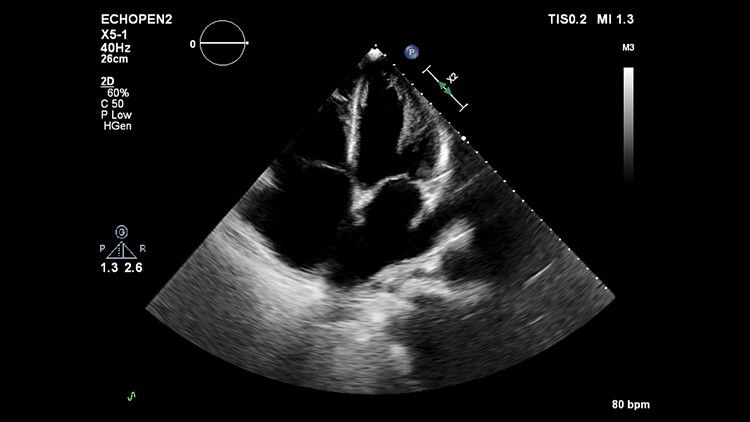

Ультразвуковая система Philips EPIQ CVx предоставляет врачу широкий спектр возможностей для еще более качественной и точной визуализации. Благодаря высокому разрешению дисплея, система обеспечивает максимальную детализацию как в 2D, так и в 3D режимах, а также при доплеровском картировании.

Ультразвуковая система Philips EPIQ CVx предоставляет врачу широкие возможности для еще более качественной и точной визуализации. Благодаря высокому разрешению дисплея, система обеспечивает максимальную детализацию как в 2D, так и в 3D режимах, а также при доплеровском картировании. Технологии Philips позволяют специалистам расположить УЗ-снимок на всей диагонали экрана в режиме реального времени без потери качества.

Система EPIQ CVx представляет собой специализированное решение для ультразвуковых исследований сердца, которое значительно улучшает функциональные возможности. Это способствует повышению качества медицинской помощи путем увеличения вычислительной мощности, обеспечения исключительного качества визуализации с более высокой четкостью и резкостью, повышения эффективности исследований, а также использования новой технологии надежного и воспроизводимого количественного анализа данных AIUS.

Качество изображения на EPIQ CVx

Монитор с технологией OLED обеспечивает четкую визуализацию анатомии сердца за счет расширенного динамического диапазона и улучшенного контраста. Каждый может увидеть изображение с высокой четкостью даже в нетрадиционных условиях, таких как операционная.